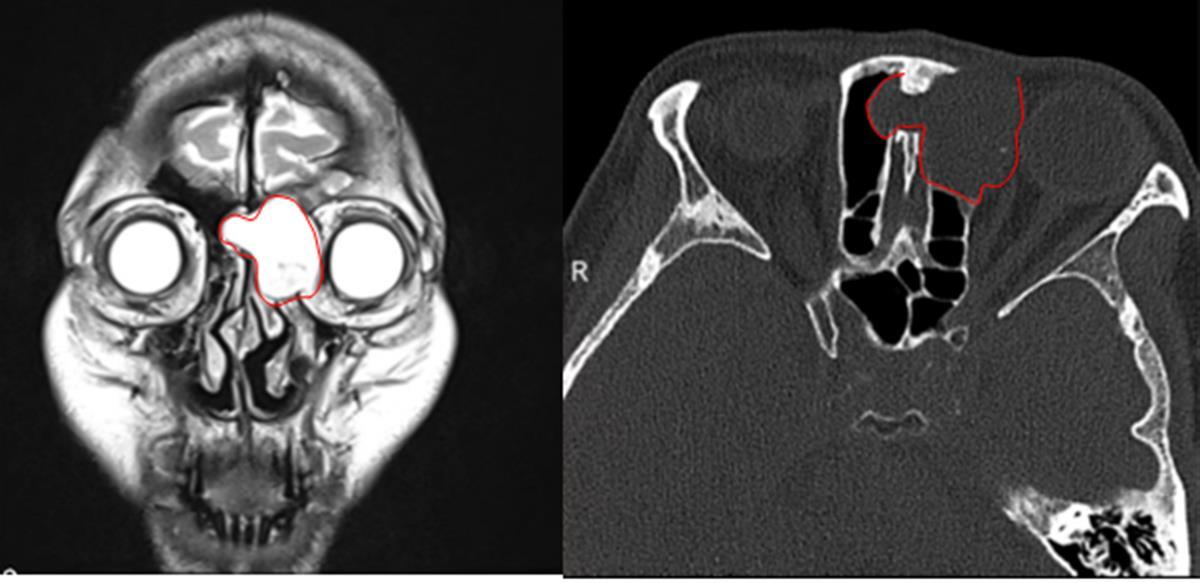

患者影像资料

经眼眶CT检查发现,周女士左眼眼眶有一个直径约2.5*3厘米的额窦肿物,挤破了眼眶骨板,造成了眼球突出。如果不及时取出肿瘤,可能很快就会出现视力进一步减退、眼球运动障碍等肿瘤压迫症状。

“其实患者的病根在鼻子里的额窦,它长大了,影响到眼球的运动,所以患者感觉到眼球胀痛,看东西重影。”该院泪道/眼鼻相关专科主任张将表示,考虑到肿瘤在眼球的侧方、靠近鼻窦,可以尝试“借道”鼻道和鼻窦,由鼻内镜来完成手术。